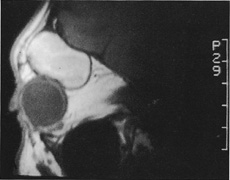

Figure 10. A. Large, well-encapsulated intraconal mass on MR scan. B. Small lateral canthotomy incision will be used to perform lateral orbitotomy and remove the intraconal mass.